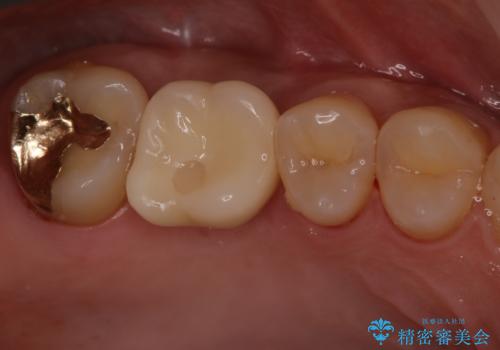

インプラント治療はブリッジと比較して、両隣の歯を削らなくてもよいというメリットがあります。

今回は両隣の歯を削りたくないとの希望がありましたので、インプラント治療を選択されました。